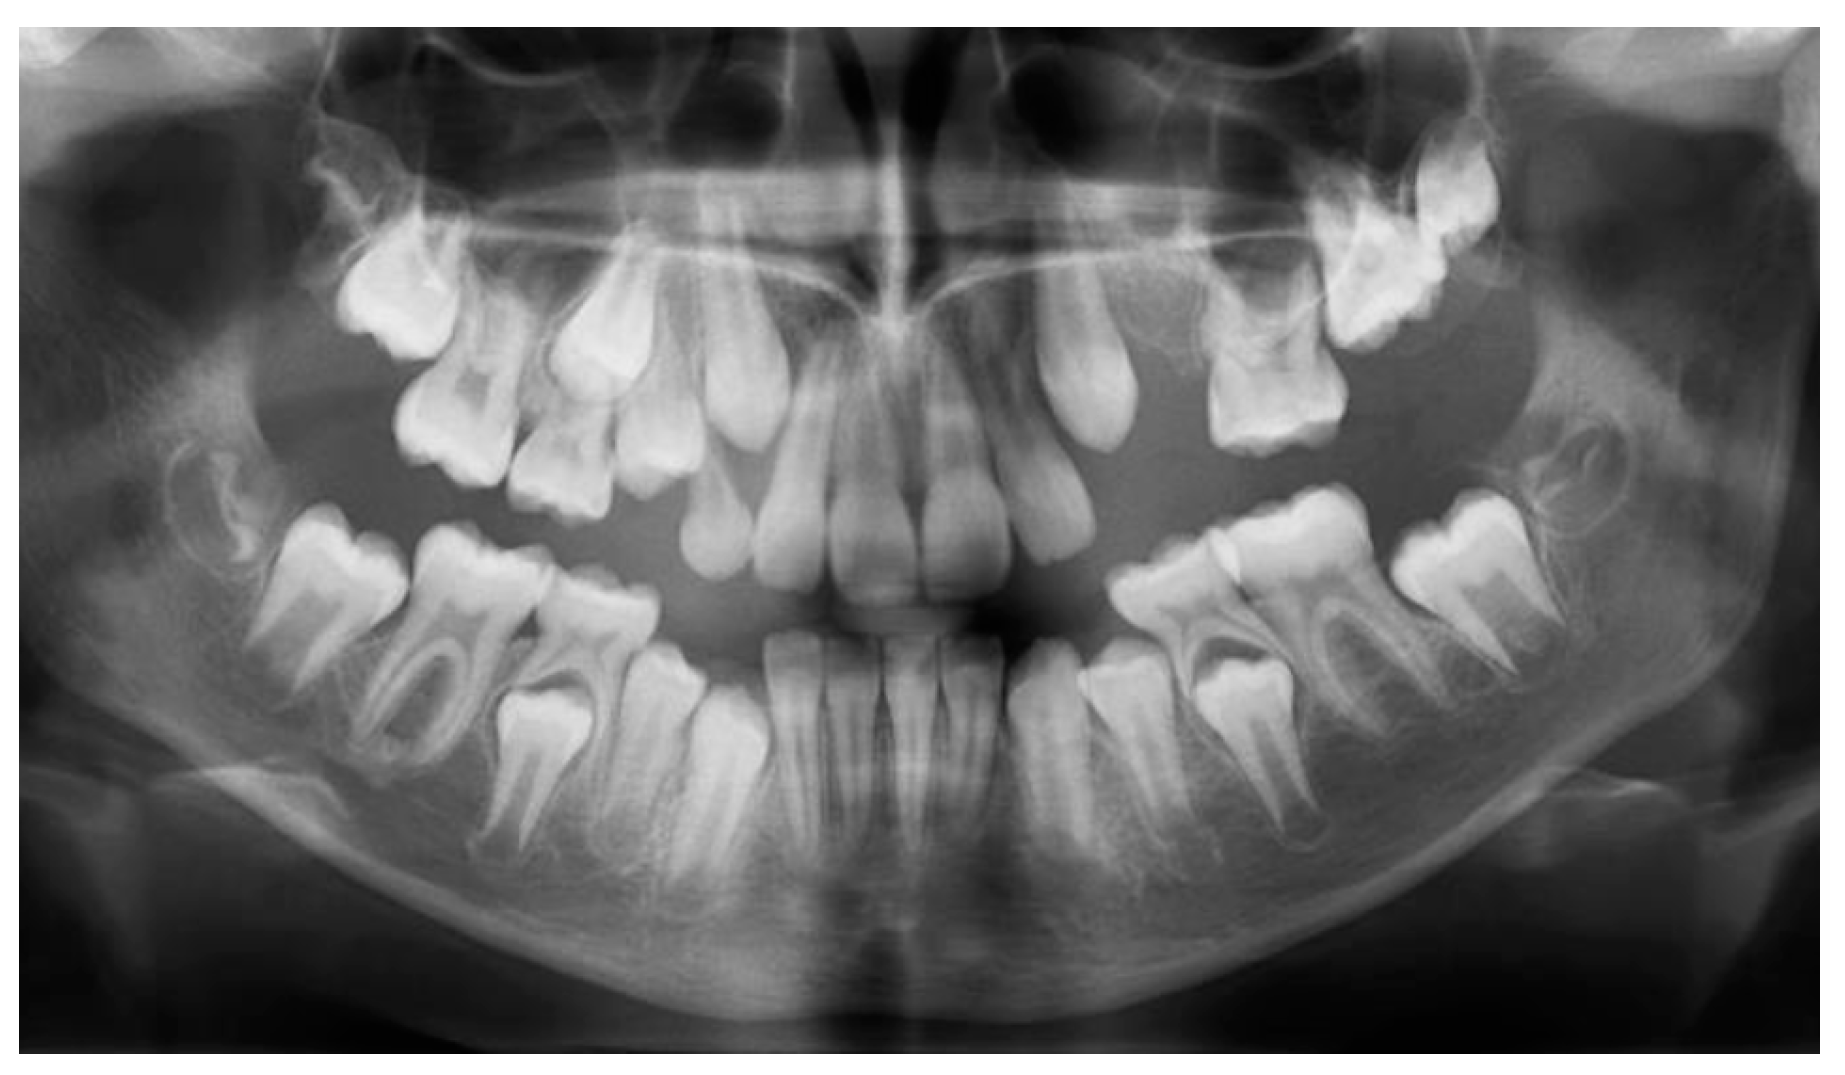

At 11y 8m, 23 was gaining its place on the arch (simultaneously with 13), 65 remained stable, while 26 and 27 seemed to continue their development very slowly within the alveolar bone (Figure 7).

Figure 7. Panoramic X-ray at age 11y 8m.